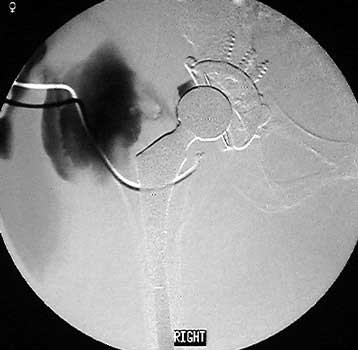

Dry tap secondary to sinus tract decompression

Sinus tract draining posteriorly